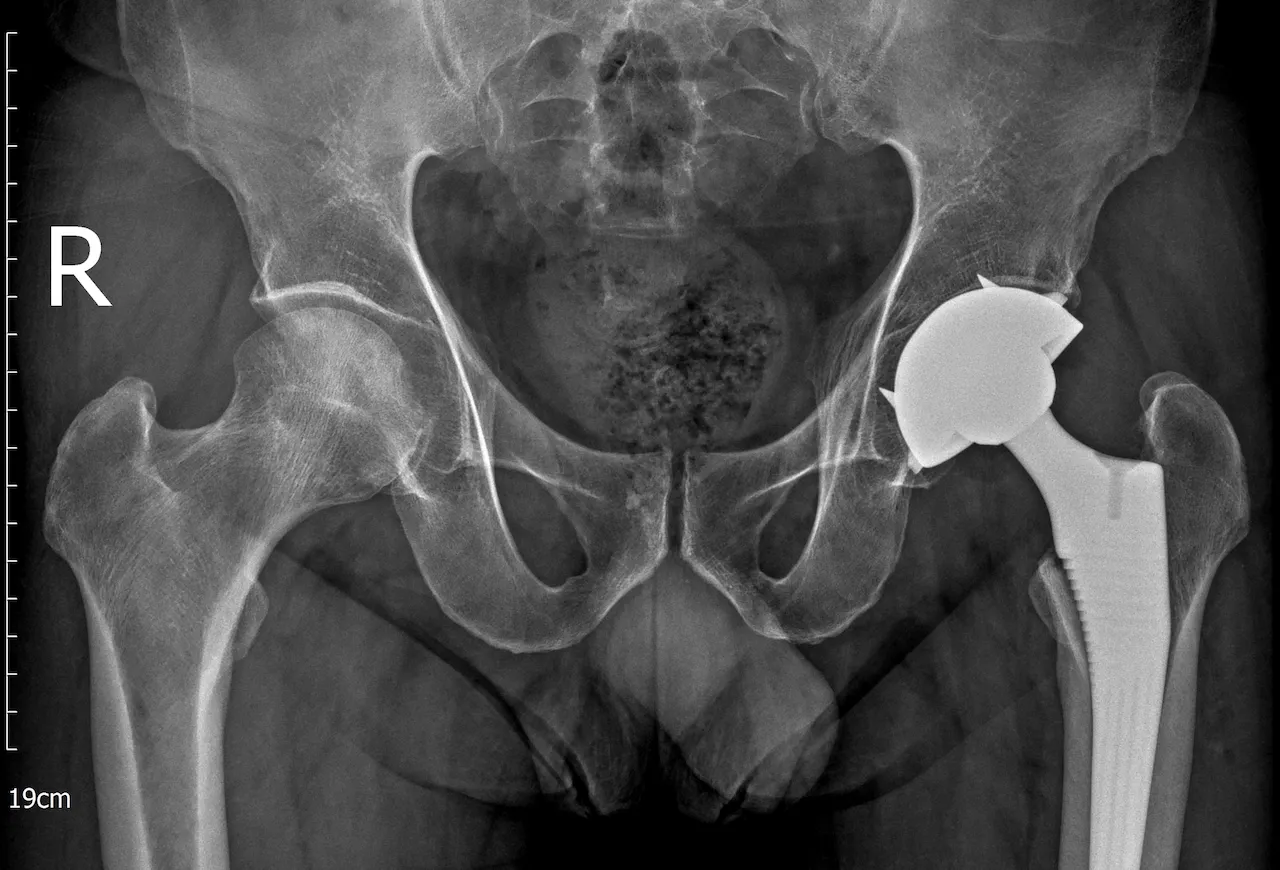

Bác sĩ đánh giá hình ảnh X-quang và phân tích mức độ tổn thương khớp

Sau khi thăm khám và đánh giá hình ảnh cận lâm sàng như X-quang, MRI, BS.CKII. Hồ Trương Đăng Triều, khoa Chấn thương chỉnh hình, Bệnh viện Hoàn Mỹ Sài Gòn nhận định: Tình trạng khớp háng bên trái của người bệnh đã tiến triển đến giai đoạn nặng không còn khả năng giữ lại, ảnh hưởng nghiêm trọng đến cấu trúc và chức năng của khớp. Việc thay khớp háng toàn phần được chỉ định nhằm phục hồi lại hình dạng của khớp, giảm đau hiệu quả và giúp người bệnh sớm quay trở lại lao động sinh hoạt như bình thường.

Hình ảnh phim X-quang người bệnh sau khi thay khớp háng